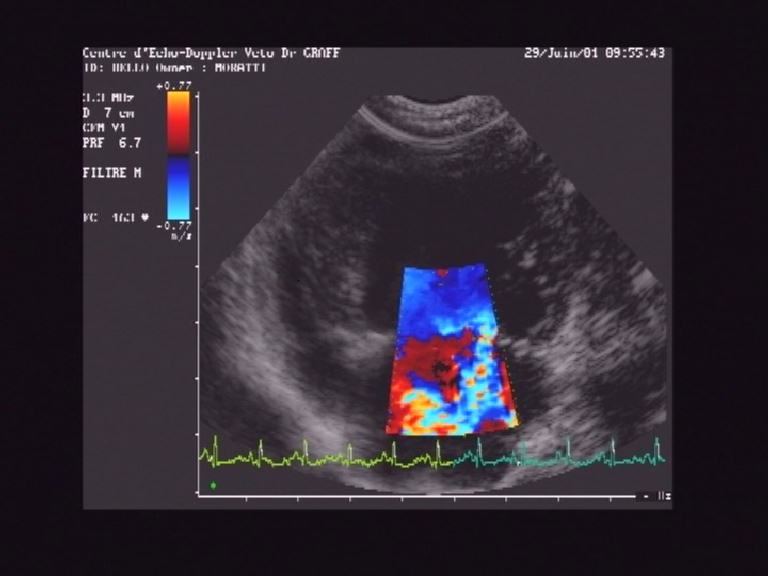

IM massive sur un chien présentant une endocardite infectieuse, le diametre de la régurgitation est important signant une IM grave      Au niveau anatomique, la valve mitrale est la valve qui ferme l'auricule gauche et le ventricule gauche au moment de la systole. Elle est composée de 2 feuillets: le grand feuillet mitral ou valve antérieure, et le petit feuillet ou valve postérieure. Ces deux feuillets s'insèrent sur un anneau à peu près circulaire, et sont retenus dans leur partie libre par des cordages qui s'insèrent dans le ventricule au niveau des piliers du VG. Les cordages interdisent aux feuillets de s'éverser dans l'auricule gauche au moment de la systole pour que la fermeture reste étanche.

IM sur un chien, vue parasternale droite grand axe, le grand flux bleu ne devrait pas existerL'echodoppler cardiaque permet de poser le diagnostic d'IM avec certitude, même si celui-ci peut parfois sembler évident. A la fin d'un examen cardiaque par echodoppler, il est possible de faire un état des lieux des lésions et evaluation de la fonction cardiaque: quantification de la fuite (de 1 à 4, suivant la gravité), importance de la dilatation des différentes cavités, mécanisme engendrant cette fuite mitrale (dilatation de l'ensemble du coeur dans le cadre d'une C.M.D, pathologie mitrale primaire type endocardiose mitrale, rupture de cordages, ou lésions valvulaires consecutives à une endocardite mitrale, par exemple), évaluation de l'efficacité cardiaque.